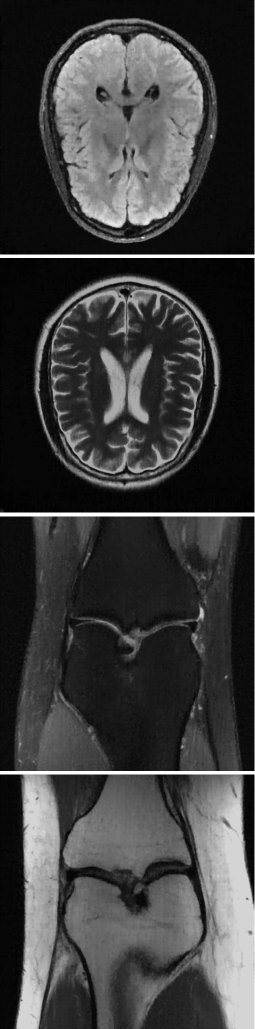

Figure 2: Comparison study: Reconstruction results in four different scans by using IFFT, CS, SL, INK, and our method.

TABLE I: Quantitative evaluation results for comparison study.

Metric IFFT CS SL INK Ours

SSIM(normal-↑\uparrow) 0.573±plus-or-minus\pm±0.069 0.521±plus-or-minus\pm±0.046 0.823±plus-or-minus\pm±0.026 0.798±plus-or-minus\pm±0.052 0.904±plus-or-minus\pm±0.030

PSNR(normal-↑\uparrow) 28.41±plus-or-minus\pm±1.395 25.59±plus-or-minus\pm±1.034 27.92±plus-or-minus\pm±2.811 28.74±plus-or-minus\pm±2.667 30.16±plus-or-minus\pm±2.966

III-B Comparison study

This subsection validates the effectiveness of the proposed method and exhibits qualitative and quantitative comparison results to other reconstruction approaches such as inverse fast Fourier transform with zero filling (IFFT), compressed sensing with total variation penalty (CS), supervised learning using TransUNet [30] (SL) and k𝑘kitalic_k-space interpolation using neural representation [31] (INK).

In Fig. 2 and Table I, qualitative and quantitative comparisons are provided. The proposed method demonstrated the superior performance rather than IFFT, CS, and INK, while SL was comparable. As far as we have implemented, the neural representation in k𝑘kitalic_k-space appears to be less effective in terms of accuracy and stability. The intensity distribution over pixels in the image domain is strongly correlated even simply in a neighborhood region. However, it is complicatedly entangled in the k𝑘kitalic_k-space domain and fairly irrelevant in a local region, which might cause the increased training complexity, learning instability, performance degradation, and etc. Compared to SL, the proposed reconstruction appears to keep anatomical details. It may be a consequence of the high adaptiveness to the given data. We further elaborate and discuss this in Section IV.

Here, CS was implemented using the open-source package, named as SigPy [32]. We trained TransUNet using supervised learning with 532 paired data, whose input is an aliased MR image and label is the corresponding image reconstructed from full sampling. For INK, a multi-layer perceptron (21) was trained, which inputs a image coordinate and outputs a two dimensional vector representing a complex-valued k𝑘kitalic_k-space intensity. The network was trained by using observed k𝑘kitalic_k-space data and then used to interpolate unsampled values in k𝑘kitalic_k-space.

It should be mentioned that the comparison with SL is not fair. We note that the reconstruction approaches other than SL do not require any training data. The use of the larger number of training data can further improve the performance of SL and even can lead it to outperform the proposed method. Most importantly, however, our method is based only on single k𝑘kitalic_k-space data.